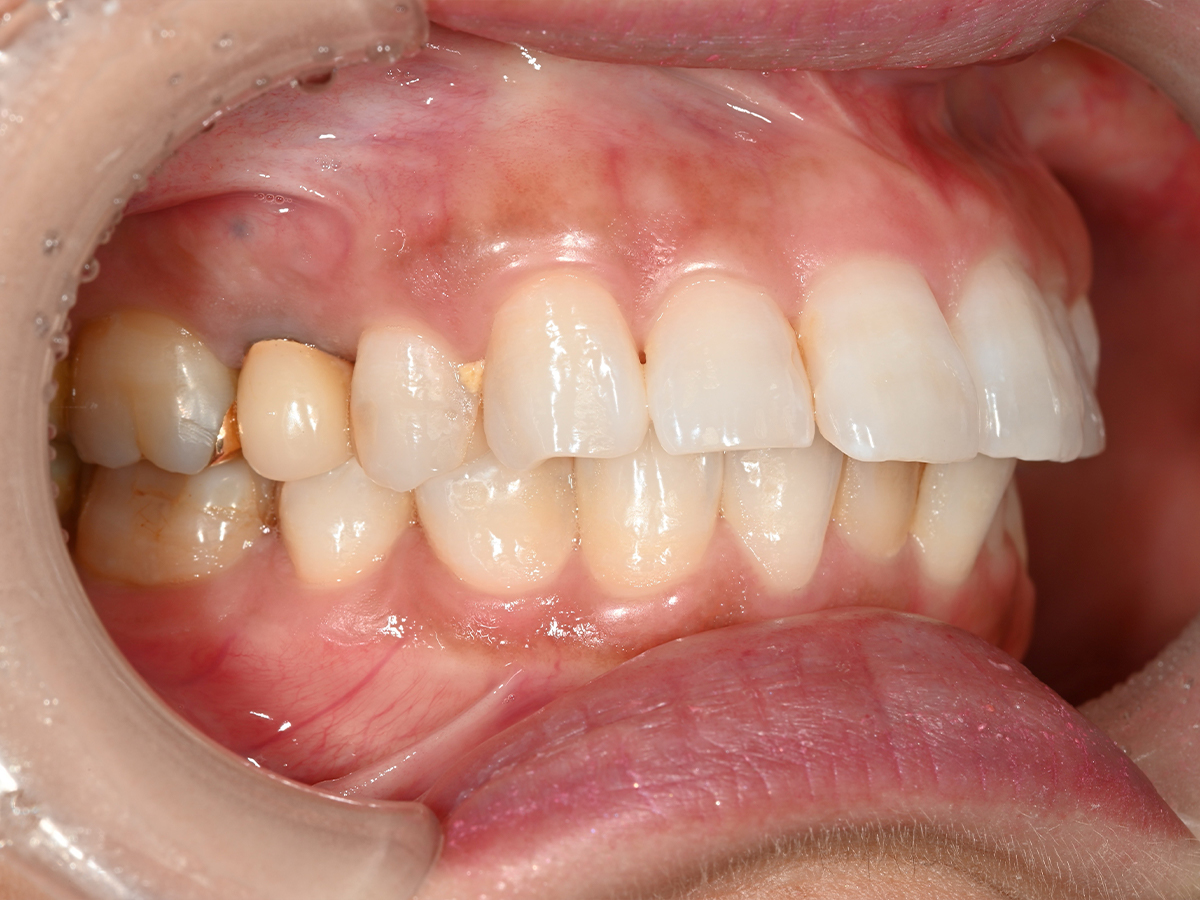

症例③

症例3_治療前 症例3_治療後

治療方法 マウスピース矯正

治療期間 1年8ヶ月

治療総額 850,000円

特記事項 抜歯なし

リスク・副作用 治療の初期段階では痛みや不快感が生じやすくなりますが、1週間前後で慣れます